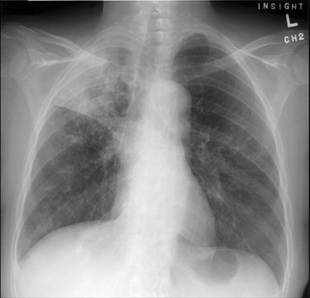

Questa malattia è chiamata ipertrofica polmonare osteopatia ed è caratterizzata da simmetrici nuove formazioni ossee sulle ossa lunghe. Sulla base della documentazione archeologica, è stato suggerito che la tubercolosi potrebbe aver causato un'epidemia migliaia di anni fa.

In questo studio, gli autori hanno esaminato settantuno scheletri umani da un sito di 7000 anni, nel sud dell'Ungheria. Hanno scoperto numerosi casi di infezioni e malattie metaboliche, e alcuni scheletri mostravano segni di tubercolosi. Si sono concentrati su uno scheletro, in particolare per verificare questa ipotesi, e hanno analizzato il DNA antico e lipidi dalle sue ossa. Entrambi i test hanno confermato la presenza del complesso batterico associato alla tubercolosi.